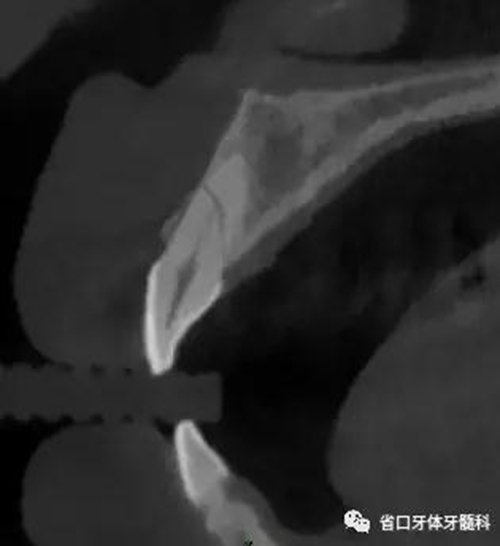

圖3:11術前CT

CBCT:11、21頸部以下均見一完全性折裂線,兩牙折裂線均位于頜骨內(nèi)且斷端移位不明顯,相應唇側(cè)骨板亦見斷裂且輕度移位。